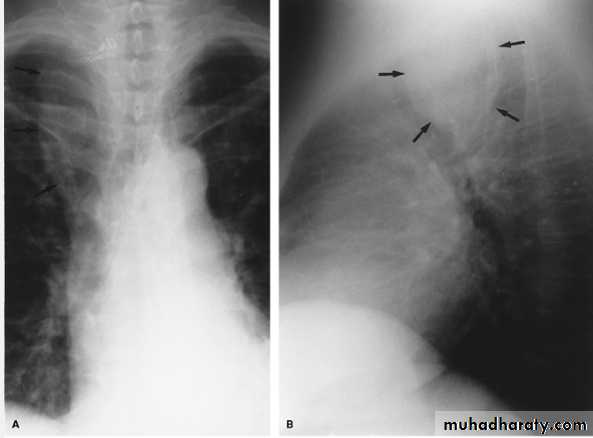

Vertical dark (lucent) lines representing air within the mediastinum are usually seen at or above the level of the aortic arch.On the posteroanterior view (A), these can be seen extending up into the lower cervical soft tissues (arrows).

On the lateral view (B), dark linear air collections can be seen in front of and behind the trachea.